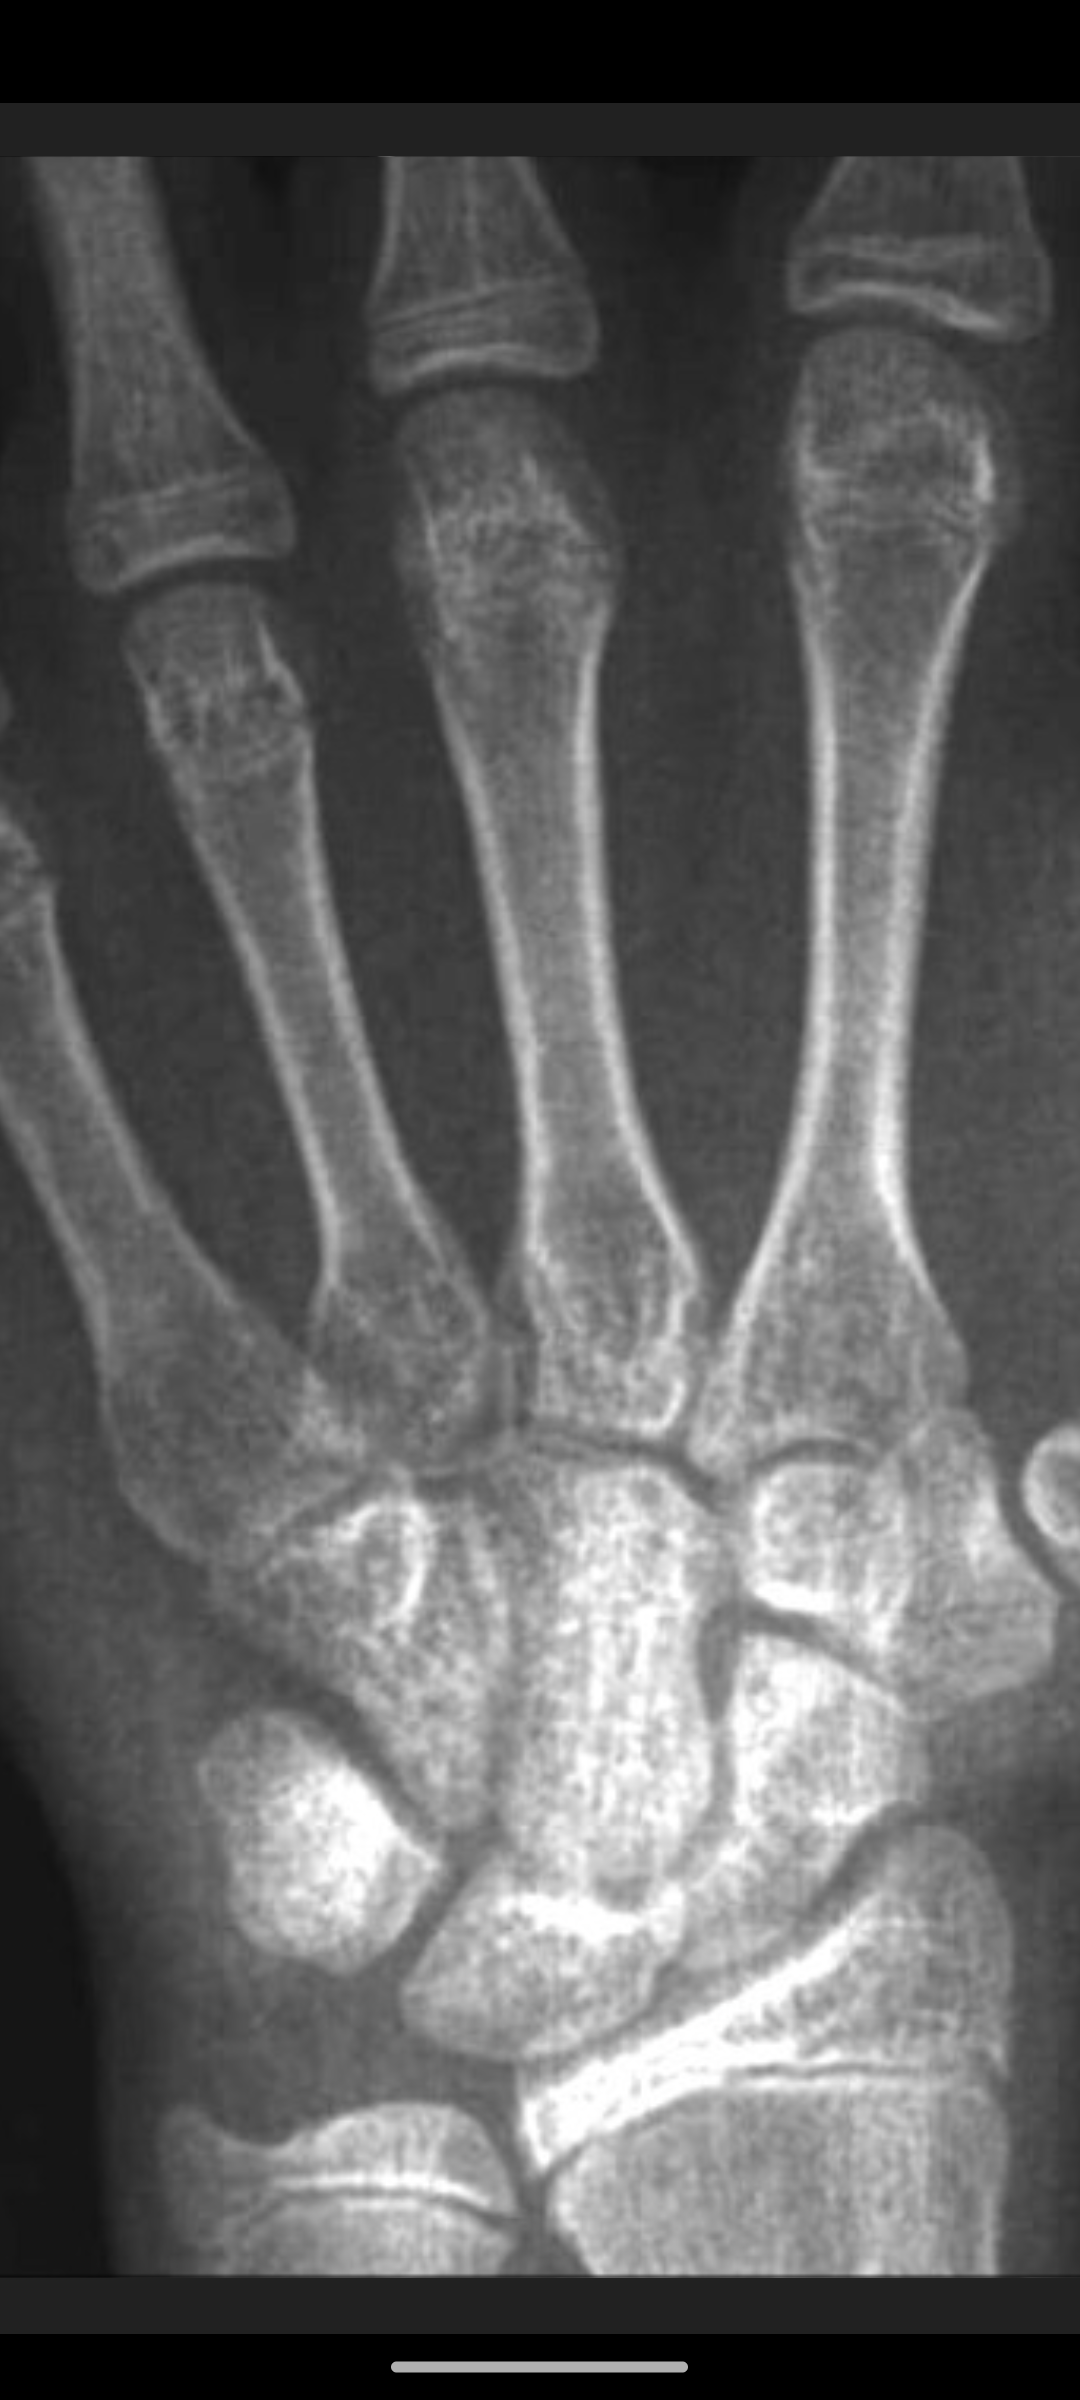

idk who did i get my genetics from. there isnt anyone thats short as me in my all family. here is my xray from 5 months ago.

X-ray is a lil blurry so try to zoom in before commenting. it looks a bit old with this quality.

Your plates are open, 183 isn't an unrealistic expectation assuming your diet and sleep schedule are good.

Hard to predict, I wouldn't say it's expected, but it's achievable